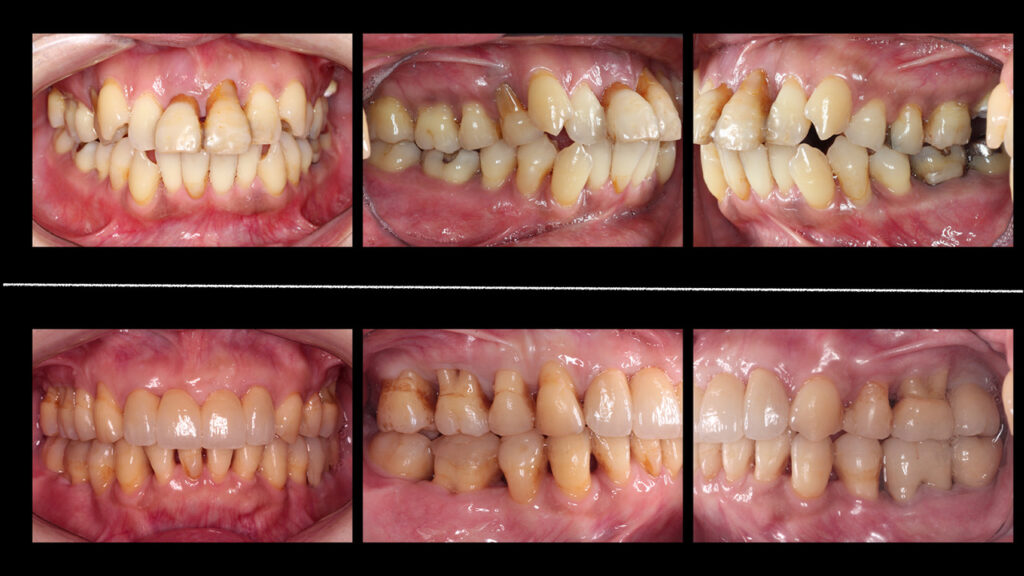

実際の治療例をご紹介します

症例1: 他院で抜歯と診断された重度歯周病を改善

患者様 60代男性

主訴 歯がグラグラして噛めない

他院での診断 全顎抜歯・総入れ歯

当院での治療 ・歯周病治療

・歯周組織再生療法

・部分的なインプラント治療

結果 8本の歯を保存することができ、しっかりと噛めるようになりました。

治療期間:10ヶ月

治療費:約90万円(保険適用部分含む)

症例1

患者様 40代女性

主訴 噛みにくい、全体的に治したい

当院での治療 ・歯周病治療(歯周組織再生療法含む)

・矯正治療

・インプラント

・口腔機能回復治療(ブリッジを含む補綴全般)

結果 自然で美しい歯になり、自信を持って笑えるようになりました。

治療期間:4年

治療費:約440万円